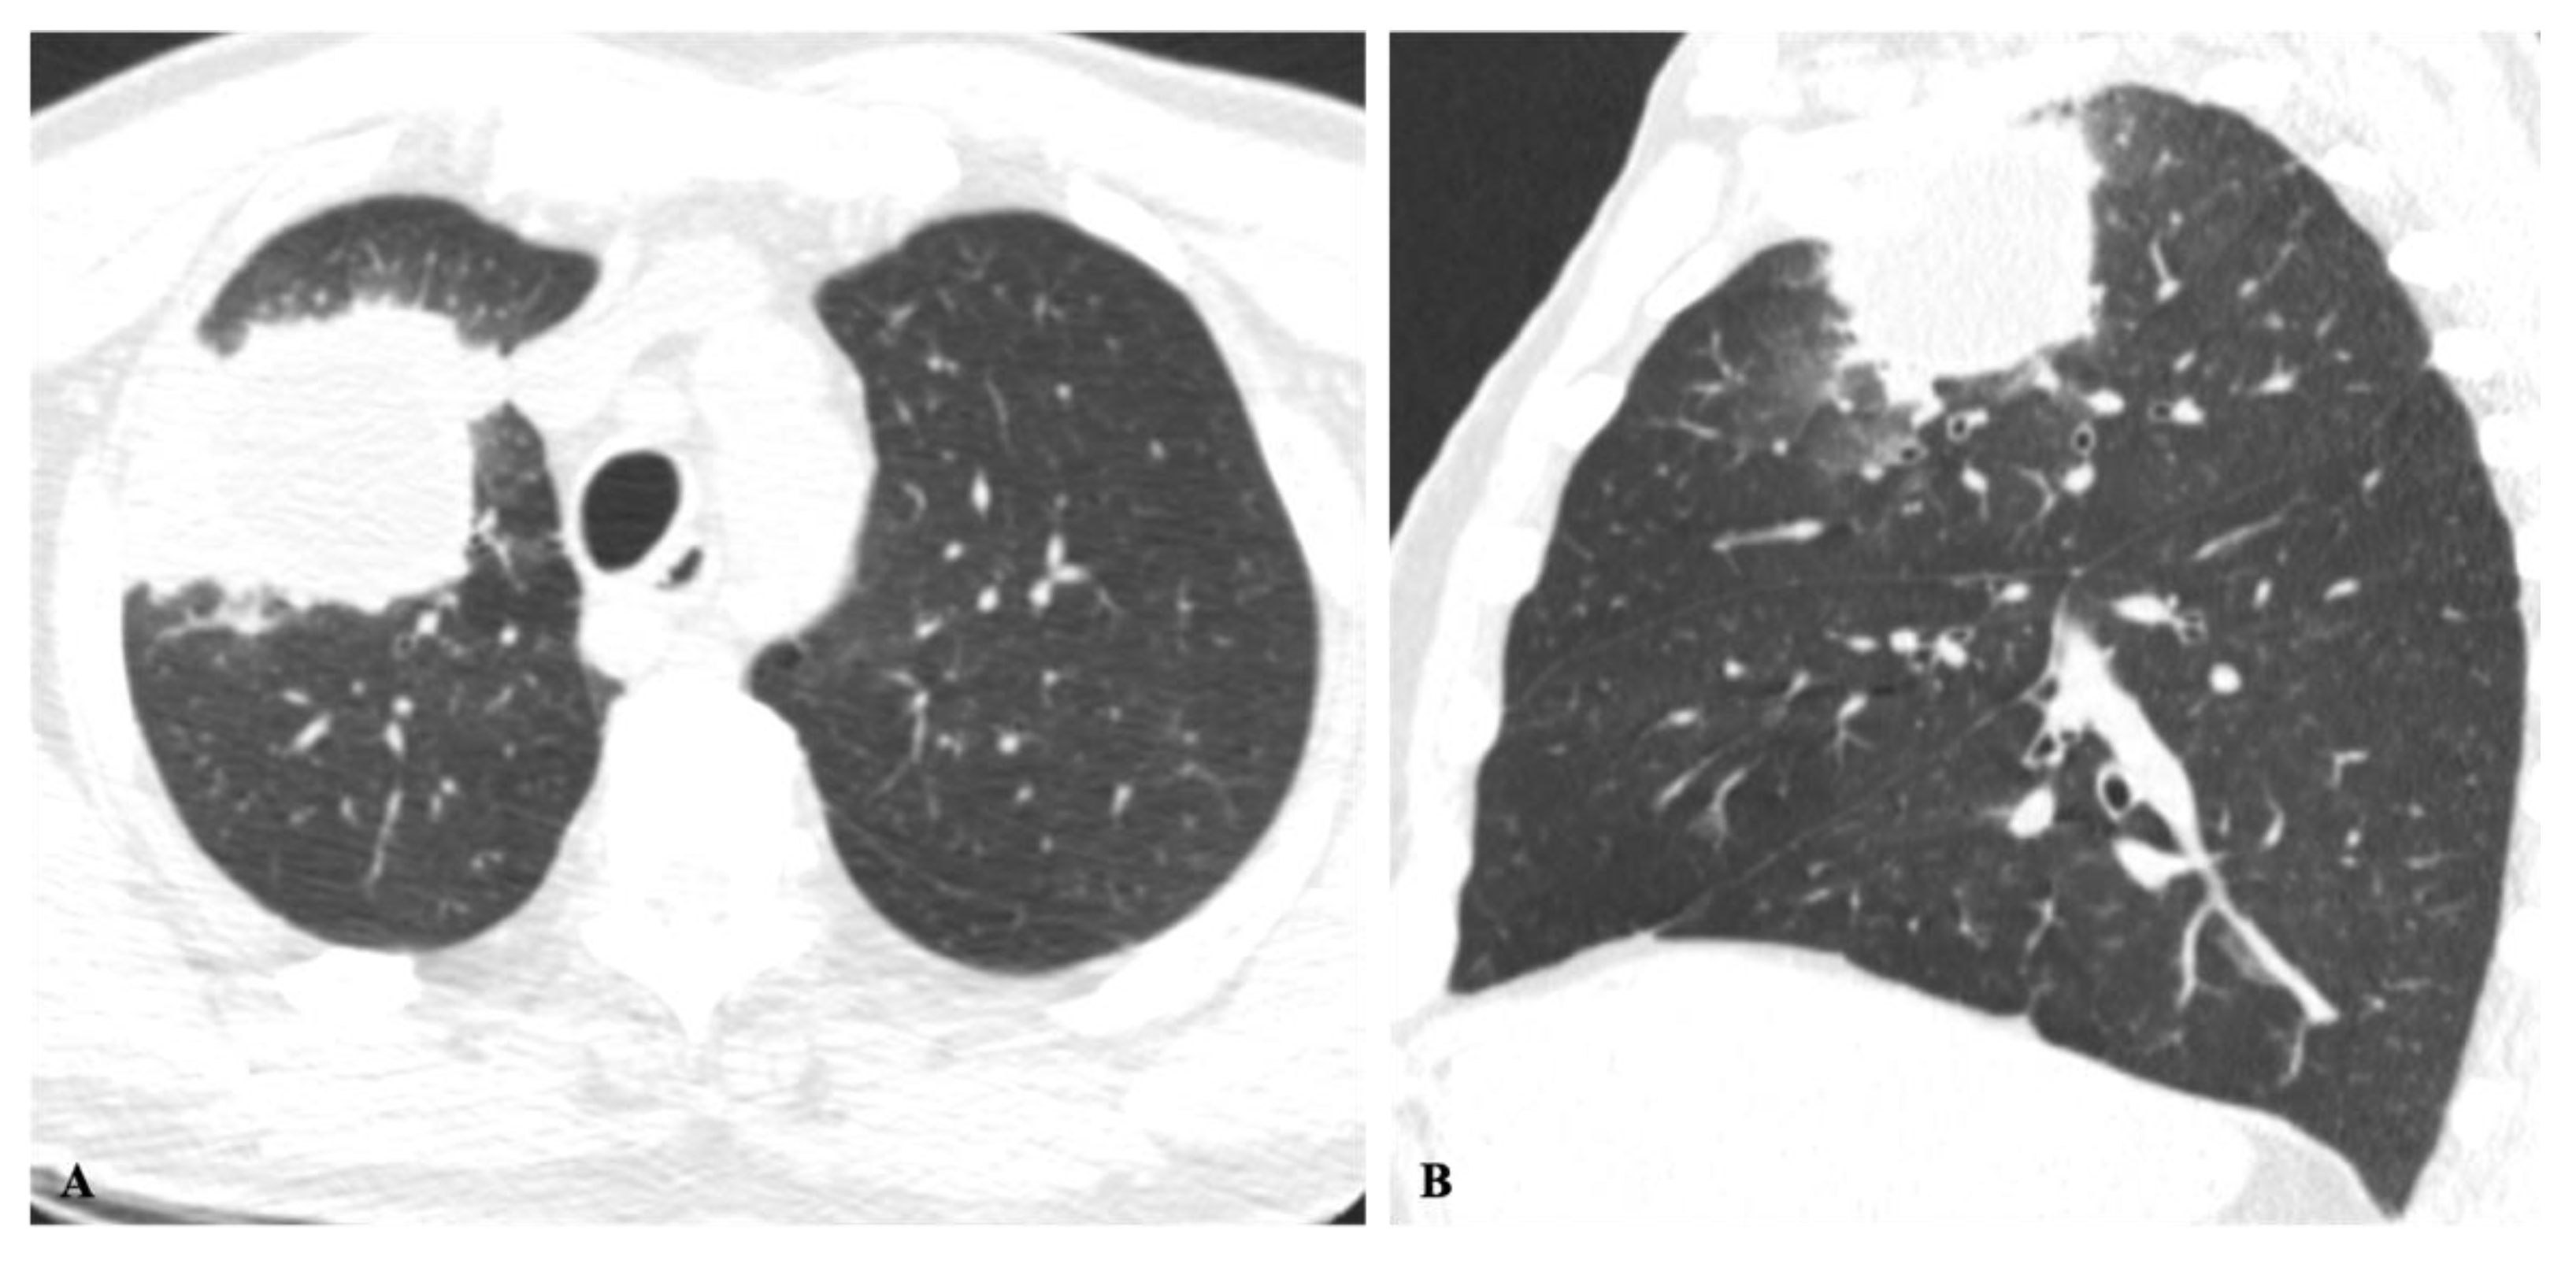

2.1. Lung Nodule or Mass

2.2. Non-Resolving Pneumonia